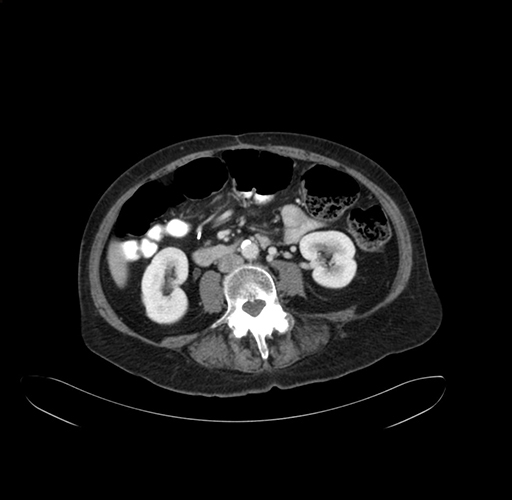

Pre-Chemo: Axial Venous